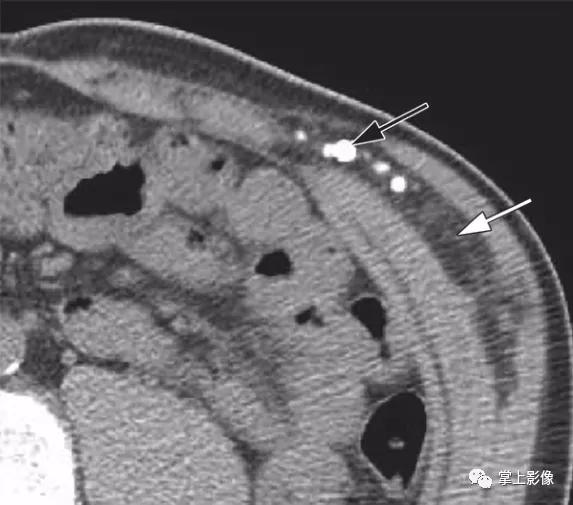

45岁男性血管瘤。轴位平扫CT示长形含脂肪肿块(白色箭头),左侧外斜肌和内斜肌之间数枚钙化静脉石(黑色箭头)。这些发现是腹壁肌肉内血管瘤的特征